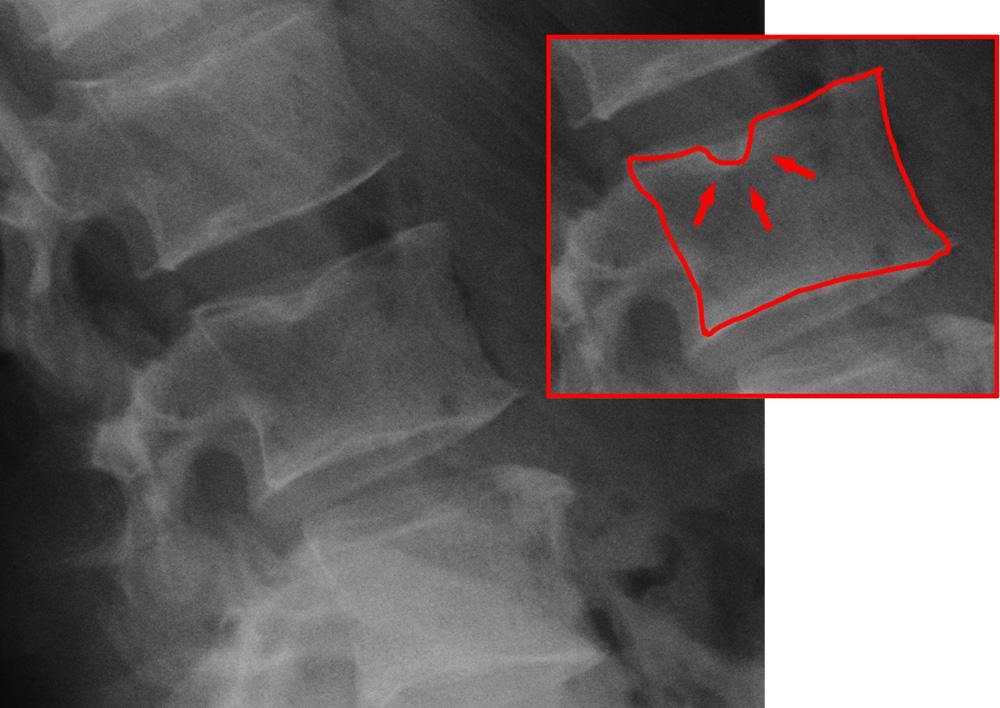

En este estudio apreciaron que las vértebras de los humanos que tienen nódulos de Schmorl son más similares a las del chimpancé, que las de humanos con vértebras sin dichos nódulos de Schmorl. Estos nódulos son protusiones (abultamientos) del disco intervertebral que se desplaza hacia el interior del cuerpo de la vértebra situada inmediatamente encima o debajo y por ello se consideran como una variedad de hernia discal y puede que en algunos medios veas que los llaman hernias discales verticales o intraesponjosas (ver foto para una mejor comprensión).

Fotos: Nódulo de Schmorl, J. Lengerke, 2010 (CET) (Praxis Dr. Jochen Lengerke) CC BY-SA 3.0,  vía Wikimedia Commons. Vértebra, Henry Vandyke Carter (dominio público), vía Wikimedia Commons. Foto de cabecera : Dominio público (CC0 Public Domain), procedente de Pixabay.